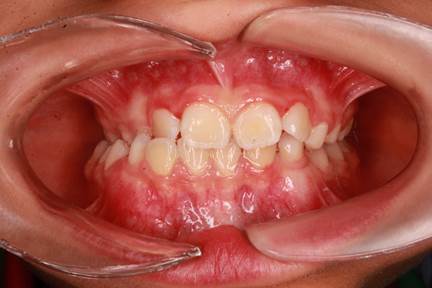

Antes del tratamiento (extraoral): El paciente presentaba una mordida cruzada con desviación mandibular hacia la derecha, lo que condicionaba la función masticatoria y la estética de la sonrisa.

Antes del tratamiento (intraoral): Se observa mordida cruzada anterior y lateral, con desviación mandibular y contacto invertido entre incisivos, lo que comprometía tanto la función masticatoria como el desarrollo del maxilar.